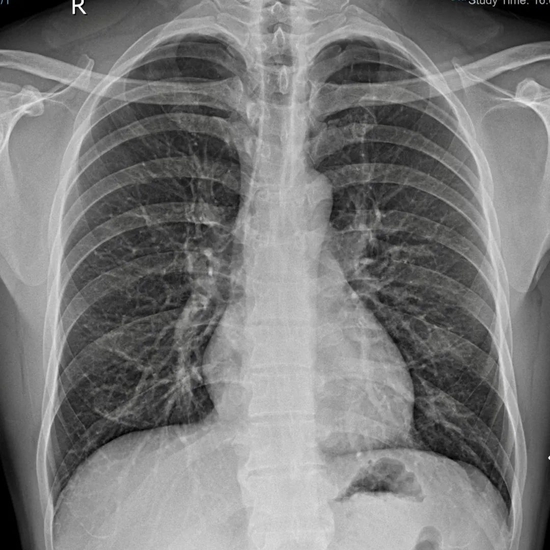

60岁的苏阿姨有一颗长反了的心脏,即与常人呈“镜像”生长,同时还患有先天性房间隔缺损和心律失常。几个月前,因活动后心慌气喘,反复心悸,来到厦门大学附属心血管病医院(简称厦心)就诊。

这是一种罕见的先天性内脏转位畸形,心尖部的朝向在胸腔的右侧,好比心脏在镜子里的“影子”,临床上称之为“镜像右位心”。

相关数据显示,先天性右位心的发生几率大概十万分之一,而合并房颤的患者,更是寥寥无几。心脏与常人呈镜像,手术操作与常规不同,这将大大增加手术难度。为此类特殊患者做手术,极大考验术者的手术操作技巧及逆向思维能力。

▲正常人的心脏位置

▲右位心的心脏位置